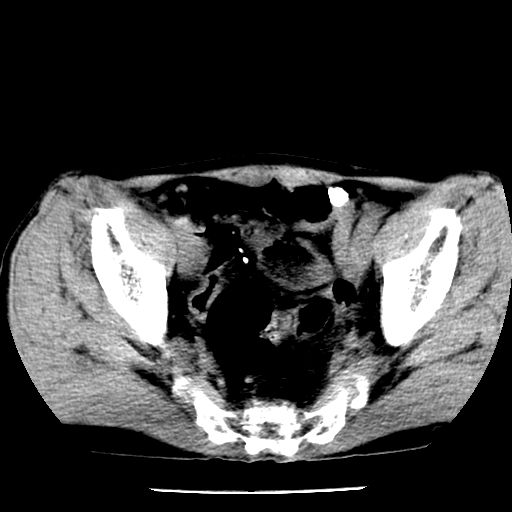

男,59岁,“结核性胸膜炎”30余年,胸部经常疼痛,多次x检查提示“肺部”炎症。腹部疼痛5日,b超提示:“肝内短管结石,余显示不清,建议进一步检查。”

两肺结核并右侧胸腔积液;脾脏、腹腔及腹膜后淋巴结结核[陈旧性];肝内胆管结石

胸部腹部都是结核(双肺。纵隔淋巴结,肝脏,脾脏,肠系膜)

两肺结核并右侧胸腔积液;脾脏、腹腔及腹膜后淋巴结结核[陈旧性];肝内胆管结石。直肠息肉?